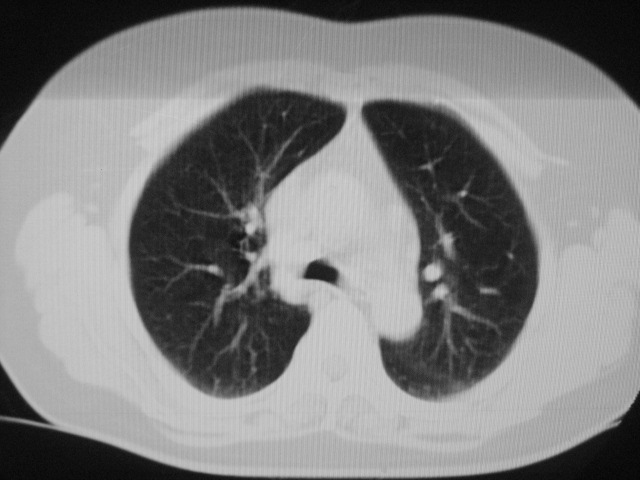

以下是引用清清楚楚在2007-8-28 7:13:00的发言:[br]右肺下叶可见斑片状高密度影,边缘模糊;右肺中叶内侧段及左肺舌段亦可见小斑片状模糊影。[br]考虑双肺感染,建议抗炎治疗后复查。

以下是引用天南地北在2007-8-27 23:49:00的发言:[br]右肺下叶可见斑片状高密度影,边缘模糊;右肺中叶内侧段及左肺舌段亦可见小斑片状模糊影。[br]考虑双肺感染,建议积极抗炎治疗后复查。

以下是引用天南地北在2007-8-27 23:49:00的发言:[br]右肺下叶可见斑片状高密度影,边缘模糊;右肺中叶内侧段及左肺舌段亦可见小斑片状模糊影。[br]考虑双肺感染,建议抗炎治疗后复查。

以下是引用难听在2007-8-28 13:17:00的发言:[br]右肺下叶背段支气管狭窄,是否可以考虑新生物伴阻塞性肺炎.请大家帮帮忙,这个病人是卫生局长的丈母娘.惹不起啊.